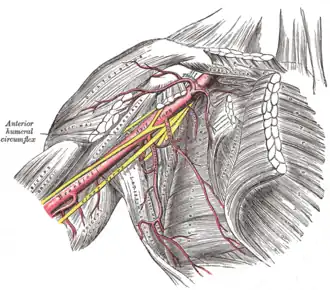

The axillary artery and its branches. The SA is seen alongside the pec minor.

The axillary artery and its branches. The SA is seen alongside the pec minor. -